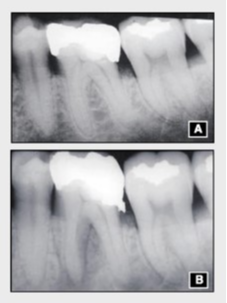

Εικ. 1: Αποκατάσταση τερηδόνας μετρίου βάθους.

Α. Φωτογραφία του 42 με τερηδόνα παρειακά, εγγύς και άπω χωρίς κανένα κλινικό σύμπτωμα, σε ασθενή ηλικίας 34 ετών. Οι δοκιμασίες ζωτικότητας ήταν φυσιολογικές.

Β. Ακτινογραφική εικόνα του ιδίου δοντιού. Παρατηρείται ότι οι διαστάσεις της πολφικής κοιλότητας και οι περιακρορριζικοί ιστοί είναι στα φυσιολογικά επίπεδα.